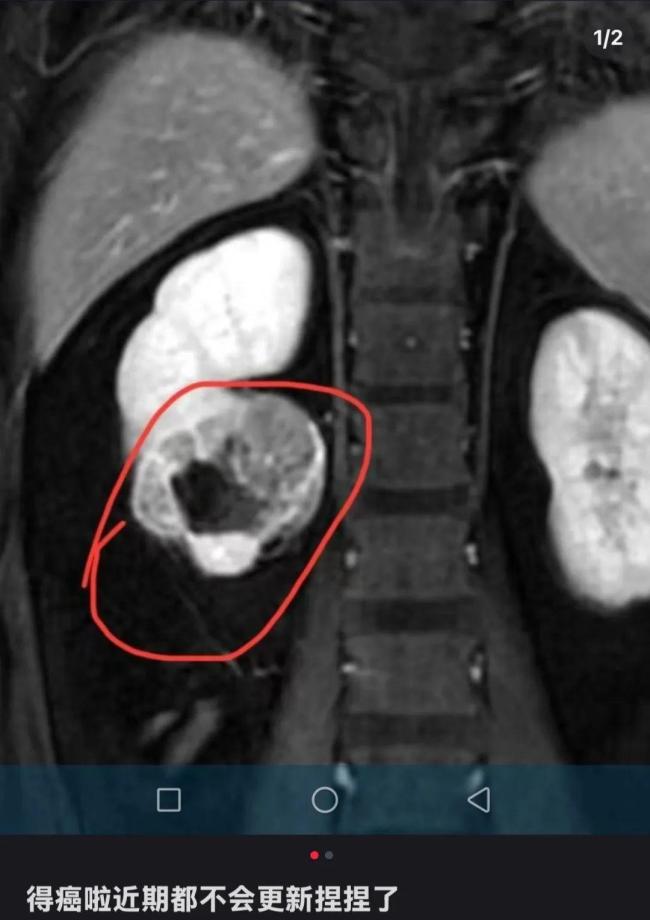

近两年,一种捏后能回弹的玩具“捏捏”走红,成为年轻人缓解压力的热门选择。然而,近日一位解压“捏捏”玩具博主自曝患癌的消息,引发公众对这种玩具潜在健康风险的关注。该博主在社交媒体上透露自己罹患肾癌,并宣布将暂时停止更新与“捏捏”玩具相关的视频内容。他最新更新透露病情:肾脏有部分坏死,即将进行手术。

据了解,该博主长期以展示捏捏玩具的揉捏过程为主,部分限量款产品曾被炒至上千元高价。虽然他在文案中并未提及具体的患癌原因,但在评论区有网友怀疑其患癌原因与长时间接触“捏捏”有关,称肾癌与二甲苯有关,之前有测评捏捏测出二甲苯。